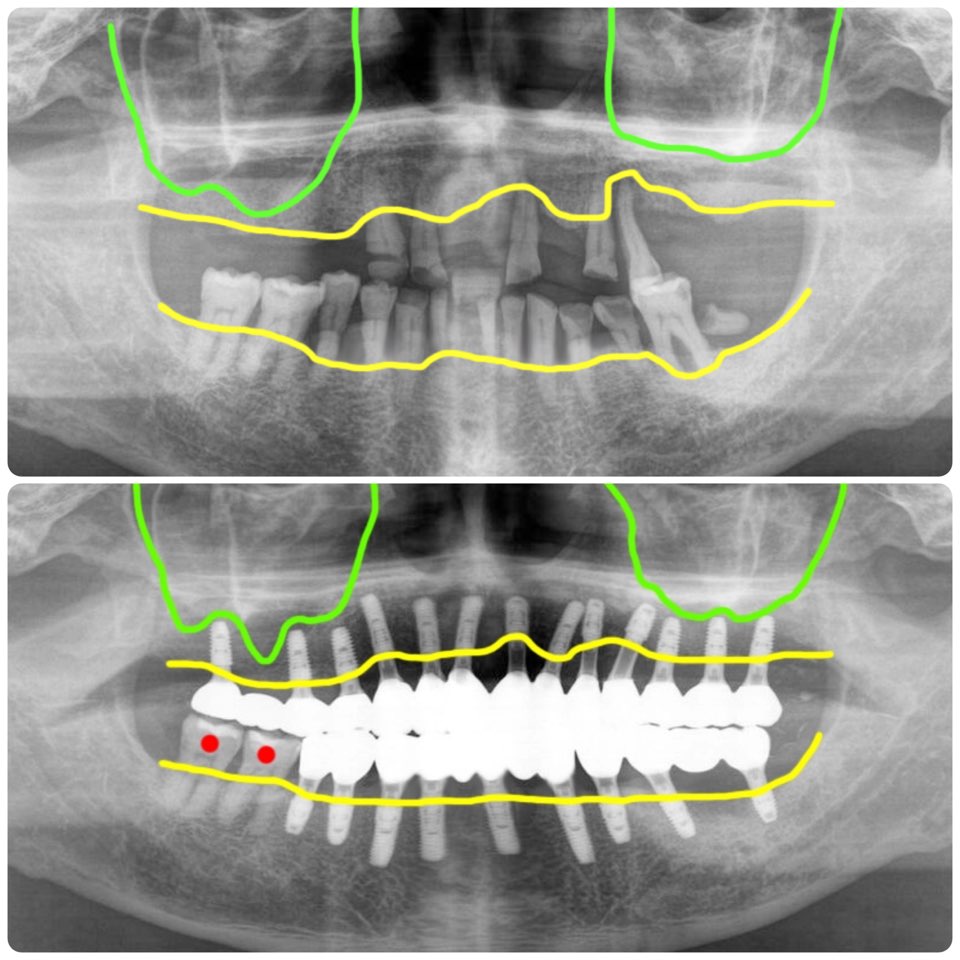

오늘 설명해 드릴 사례는 뼈가 약간 부족하지만 추가적인 대량의 뼈이식없이 간단한 뼈이식으로 전체임플란트를 빠르게 마무리한 사례입니다.

이 분은 제주도에 거주하시는 60대 남자분이셨어요. 흡연을 하시는 분이었구요. 아무래도 원거리에 있기 때문에 잦은 내원이 힘든 부분과 흡연을 한다는 점을 감안해서 치료계획을 세웠습니다.

치료기간 3개월 뼈이식추가비용없이 전체임플란트 치료완료

이렇게 해서 이 환자는 총 4회 방문 총 치료기간 3개월에 전체임플란트 치료를 완료했습니다. 제주도에 거주하는 관계로 2차 본을 뜨고 다음날 최종보철을 세팅해 드렸습니다.